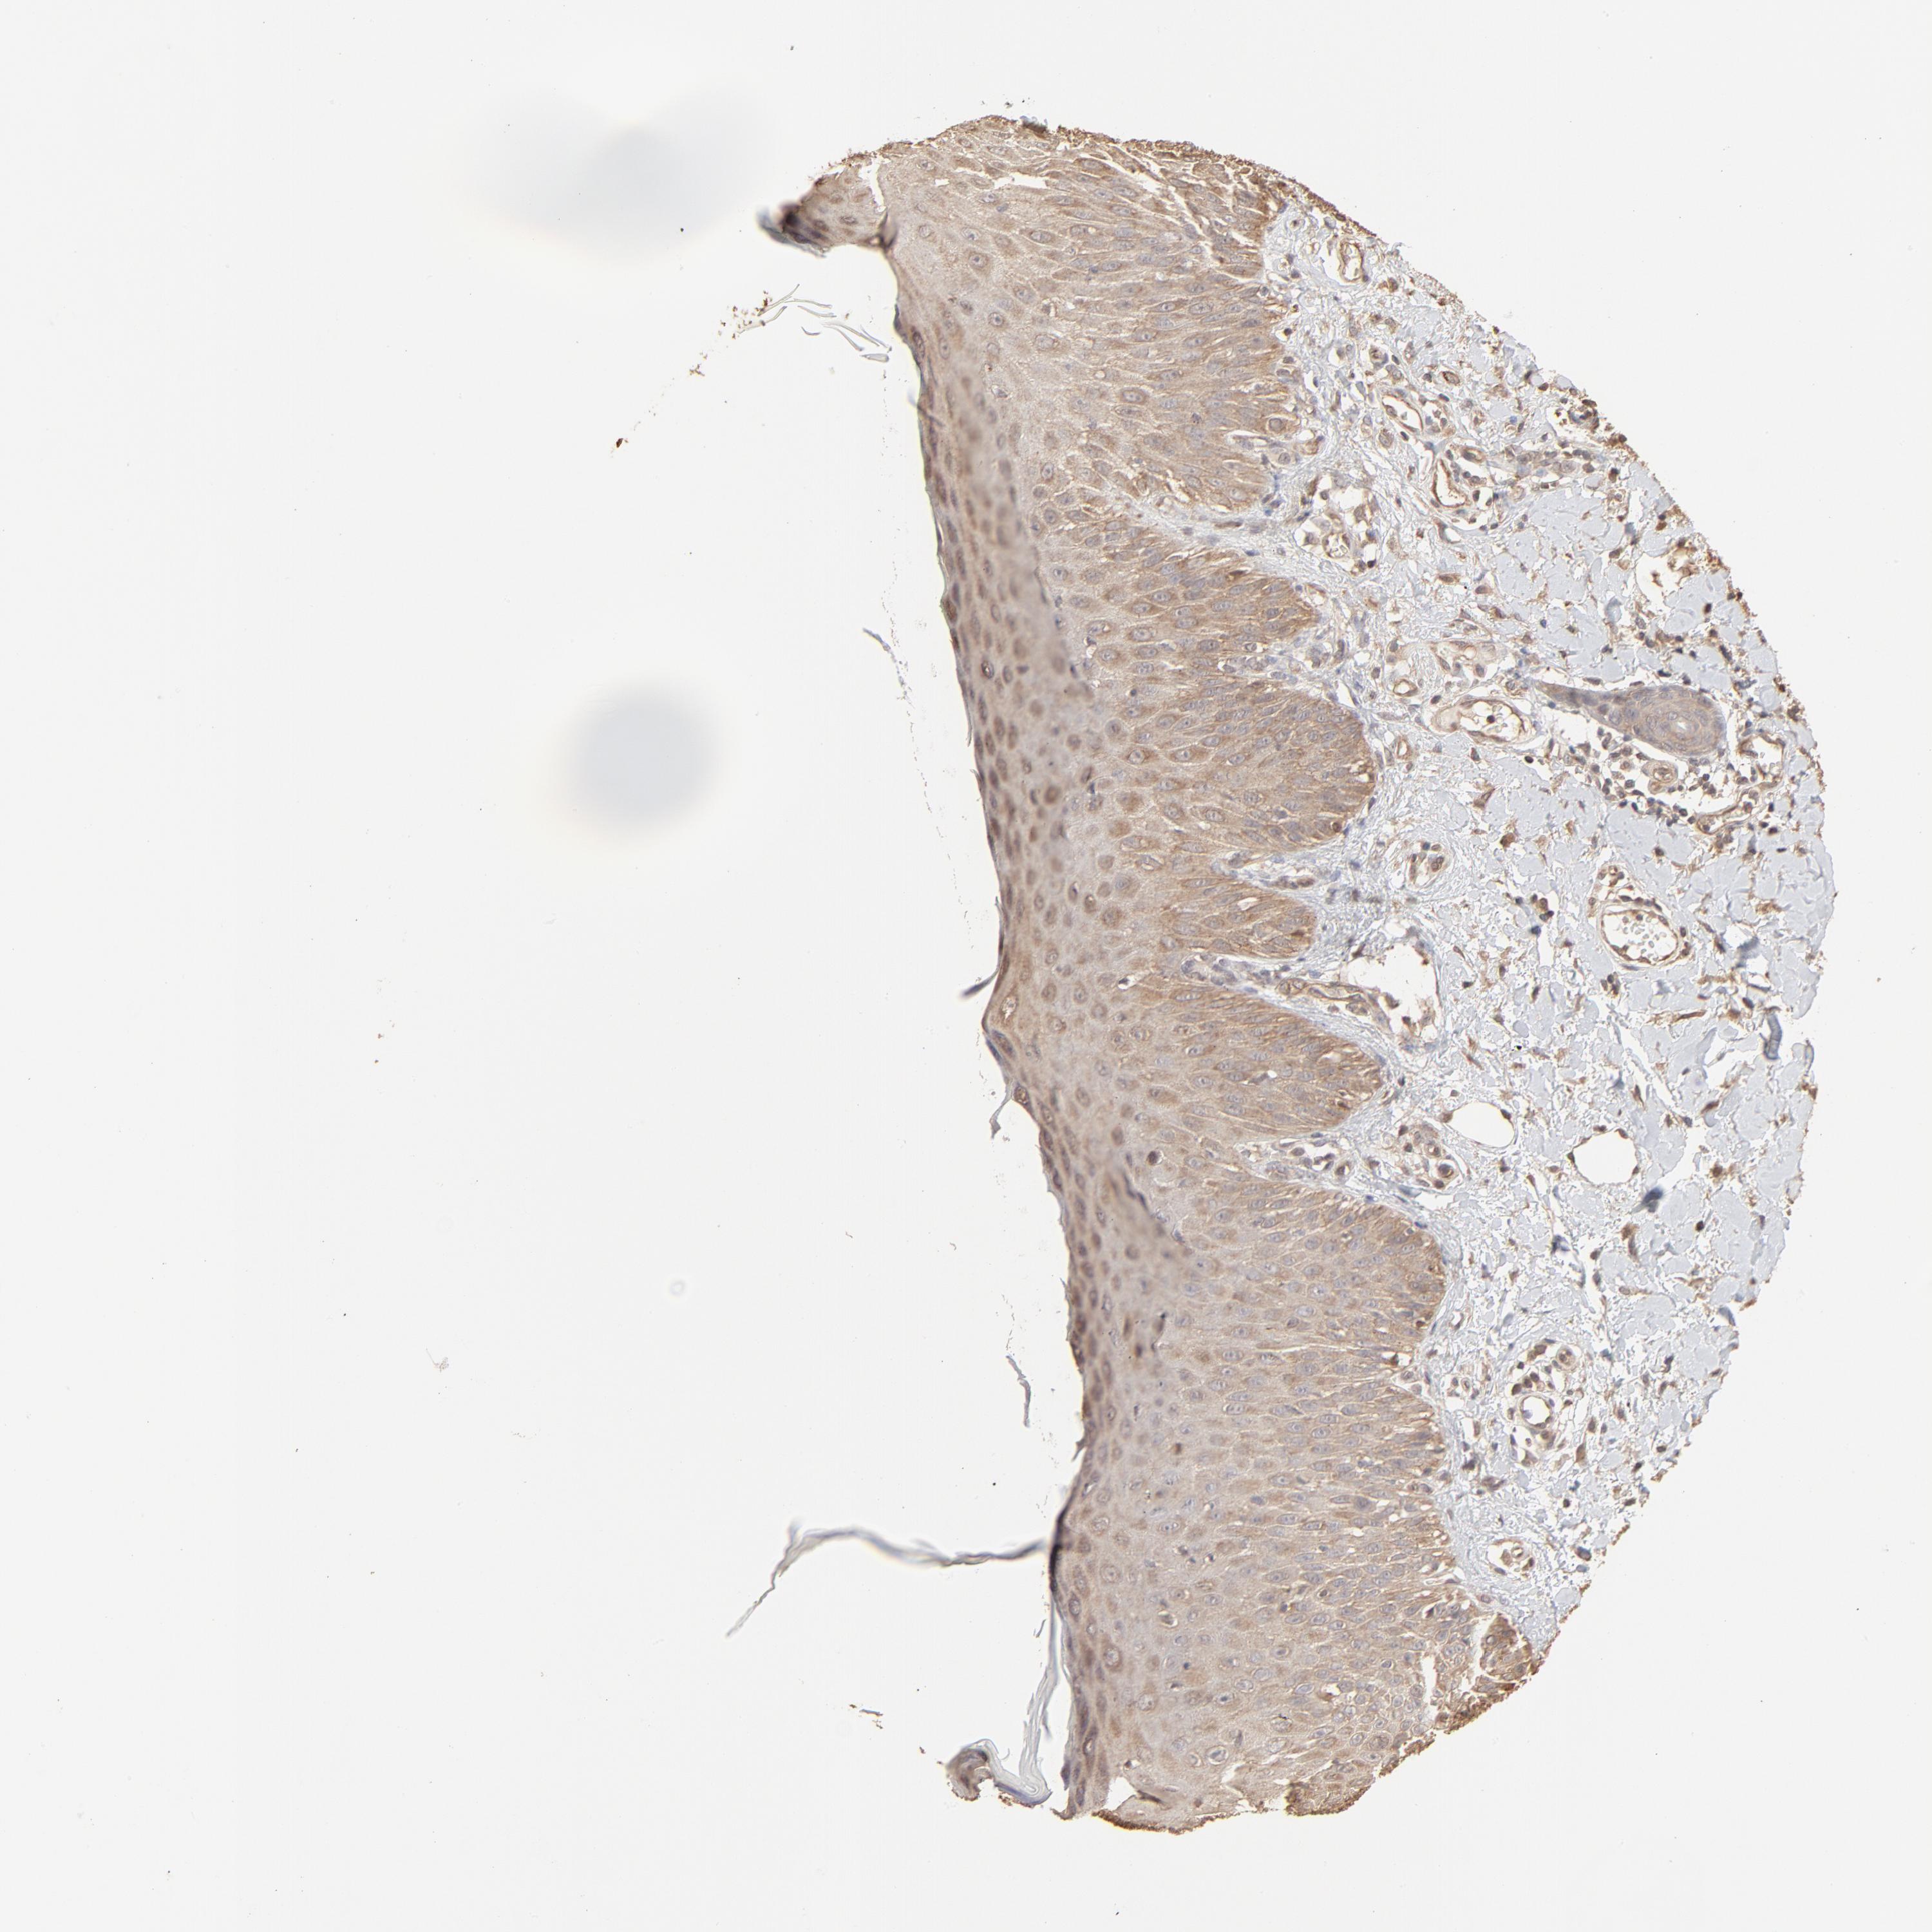

CANCER SKIN CANCER Show tissue menu

Basal cell and squamous cell cancer

SKIN CANCER - Protein expressioni

A mouse-over function shows sample information and annotation data. Click on an image to view it in a full screen mode. Samples can be filtered based on level of antibody staining by selecting one or several of the following categories: high, medium, low and not detected. The assay and annotation is described here.

Antibody stainingi

Antibody staining in the annotated cell types in the current human tissue is reported as not detected, low, medium, or high, based on conventional immunohistochemistry profiling in selected tissues. This score is based on the combination of the staining intensity and fraction of stained cells.

Each image is clickable and will lead to virtual microscopy that enables deeper exploration of all samples and also displays staining intensity scores, fraction scores and subcellular localization as well as patient and tissue information for each sample.

Antibody HPA043236

Antibody CAB003848

Staining

High

Medium

Low

Not detected

Intensity

Strong

Moderate

Weak

Negative

Quantity

>75%

75%-25%

<25%

None

Location

Nuclear

Cytoplasmic/membranous

Cytoplasmic/membranous,nuclear

Basal cell carcinoma

Squamous cell carcinoma, NOS

Squamous cell carcinoma, metastatic, NOS